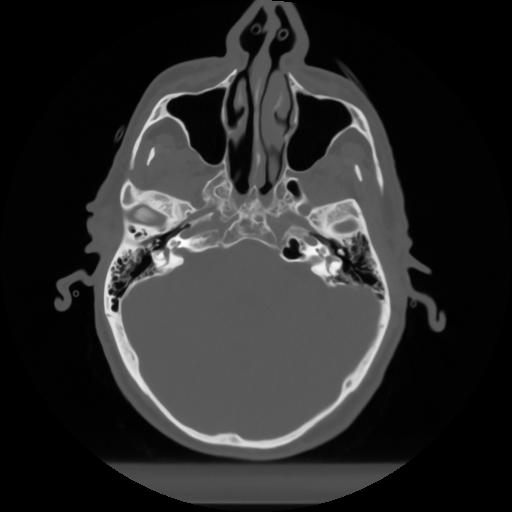

10 P.BLANDAS,,Axial,2.0,P.BLANDAS,,